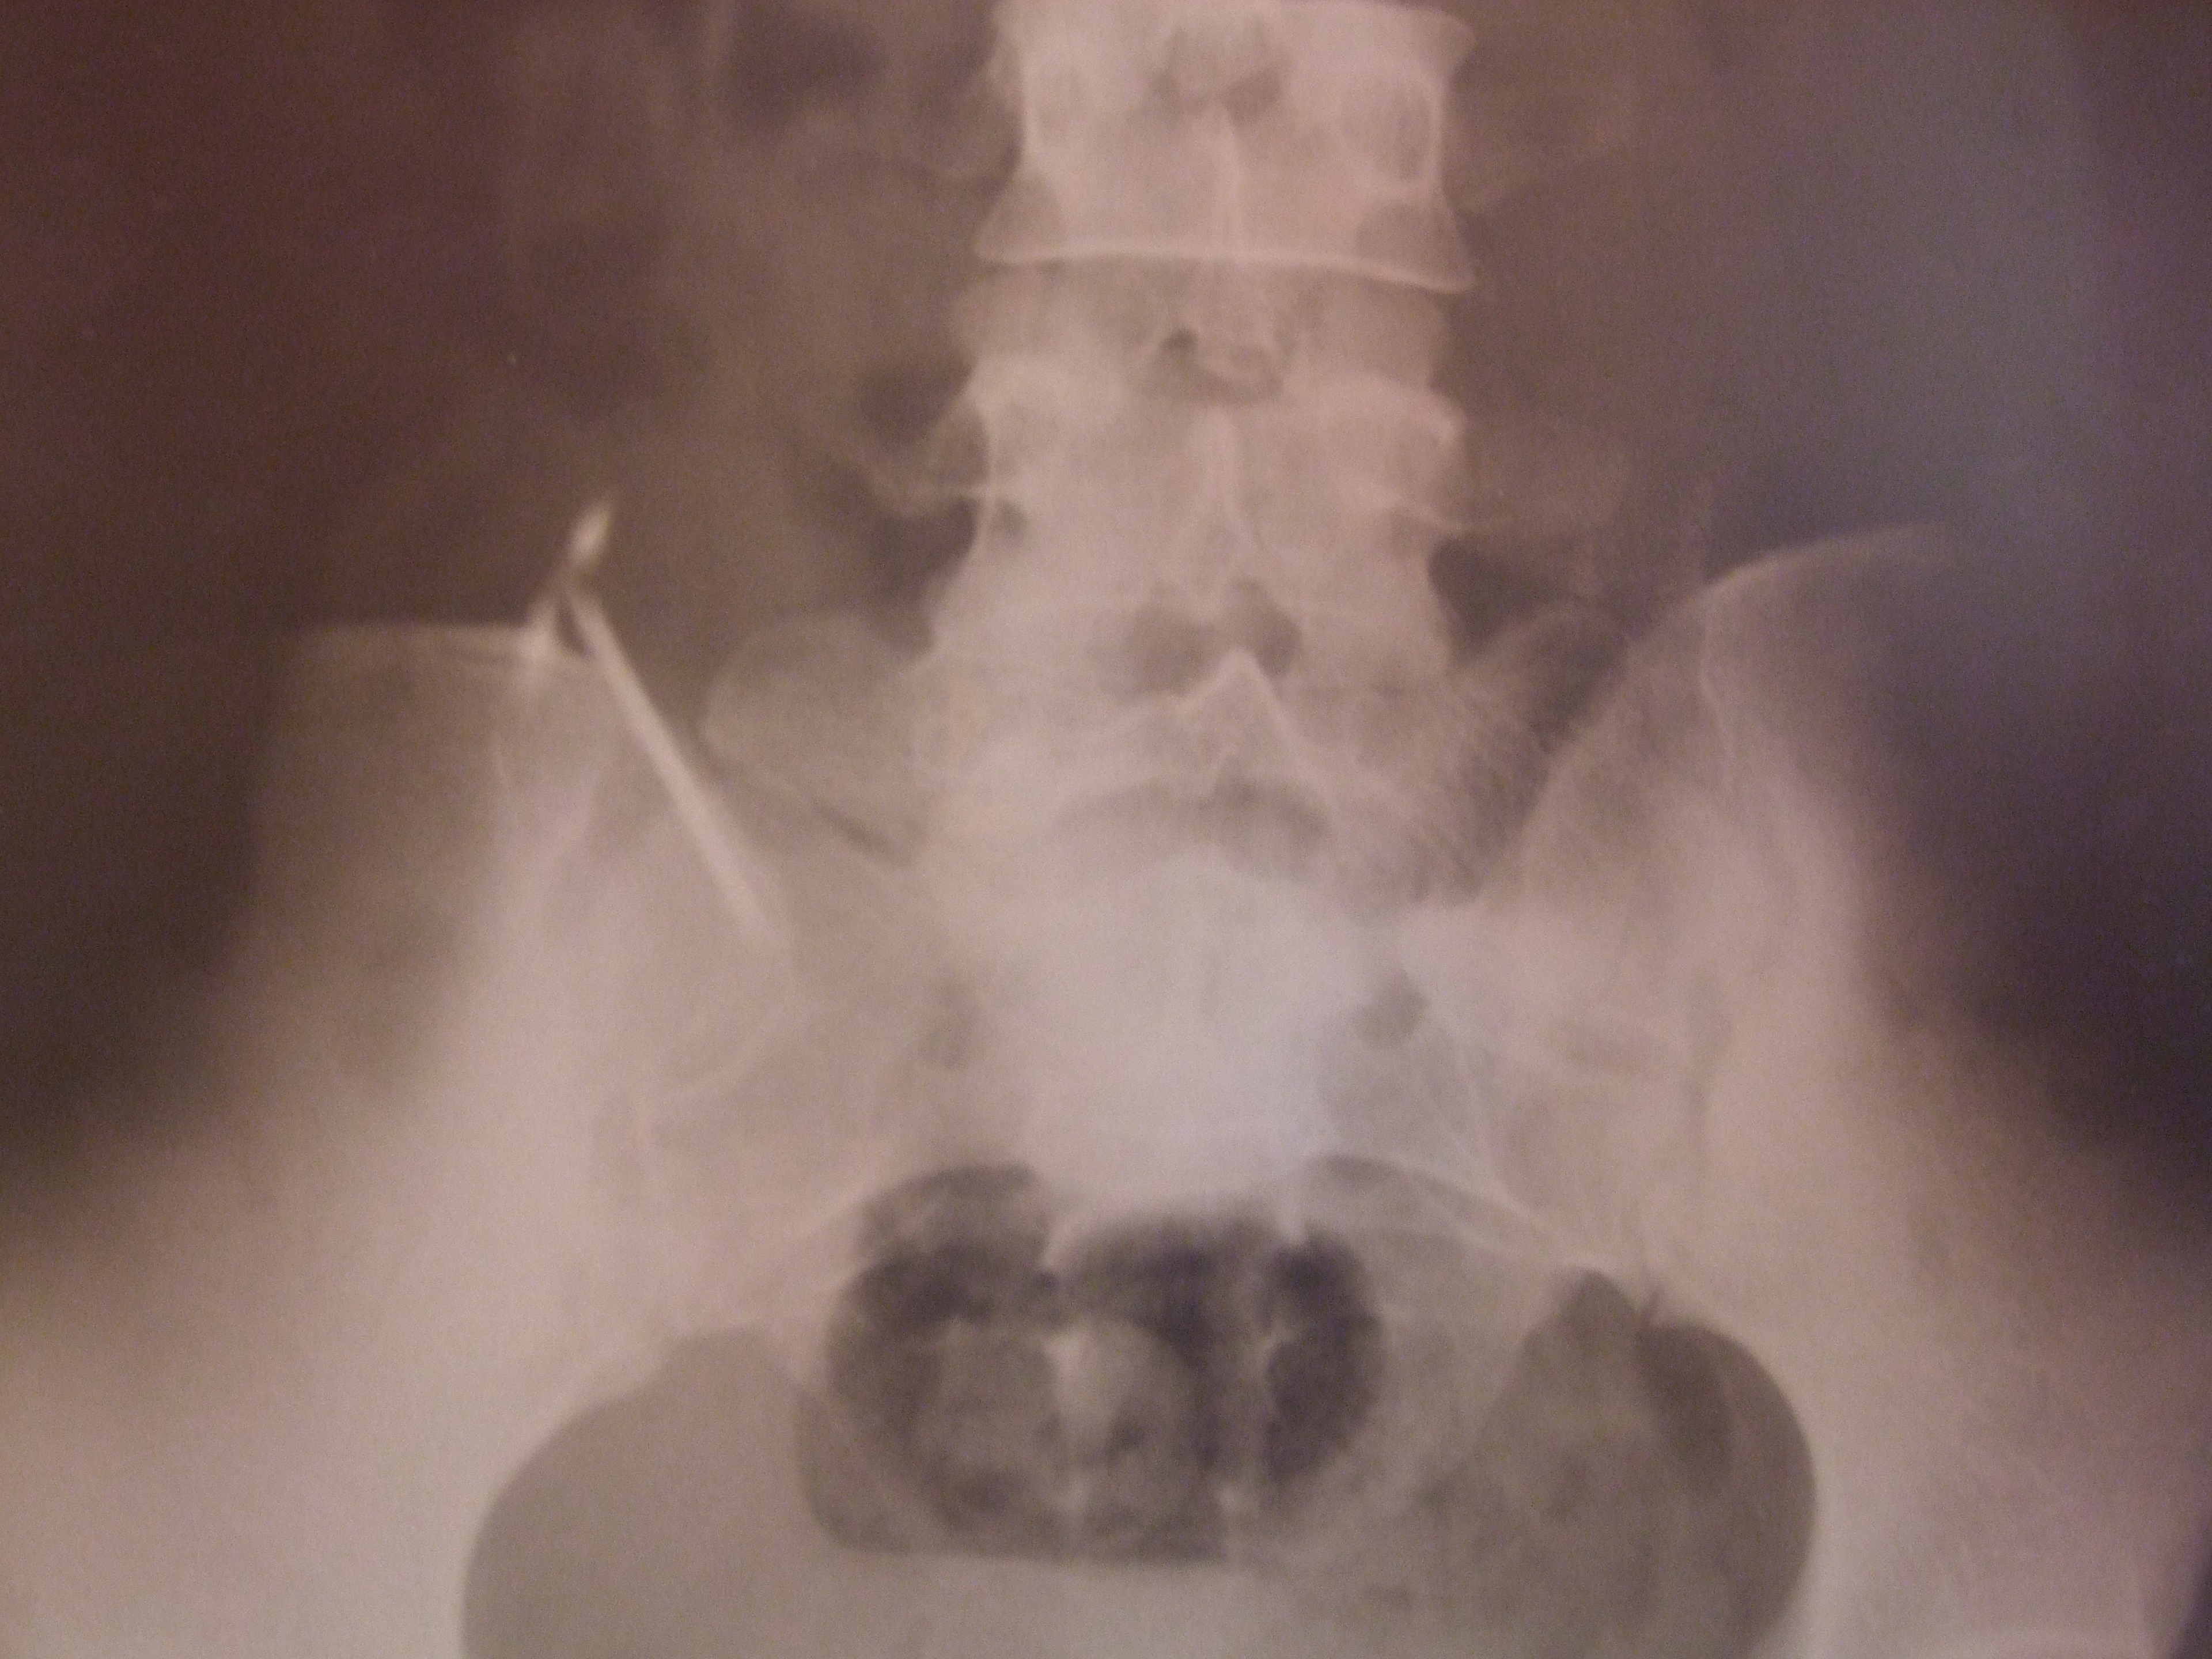

![]() |

| Hình ảnh chụp X-quang cho thấy vòng tránh thái lọt xuống ổ bụng. |